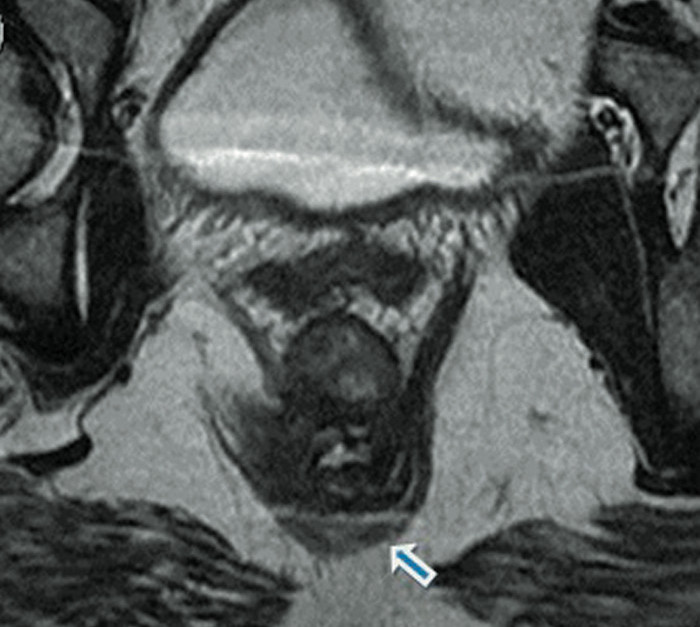

De acuerdo con el periódico, la paciente –no identificada– acudió al centro médico por sufrir abscesos en su parte trasera. Al examinarla, los especialistas se llevaron la sorpresa de encontrar no uno sino dos agujeros anales, en una evidente y rara malformación del tracto digestivo.

Fisiológicamente, la materia fecal pasa a través del canal anal, que se conecta directamente con el recto, donde se almacenen los residuos antes de dejar el cuerpo. En teoría, la mujer podría haber sido capaz de excretar a través de ambos canales. No obstante, los médicos determinaron que su segundo canal, de tan solo 3 centímetros de profundidad y un centímetro de ancho, no estaba vinculado con la pared rectal, aunque se hallaba separado del canal principal sólo por la piel.